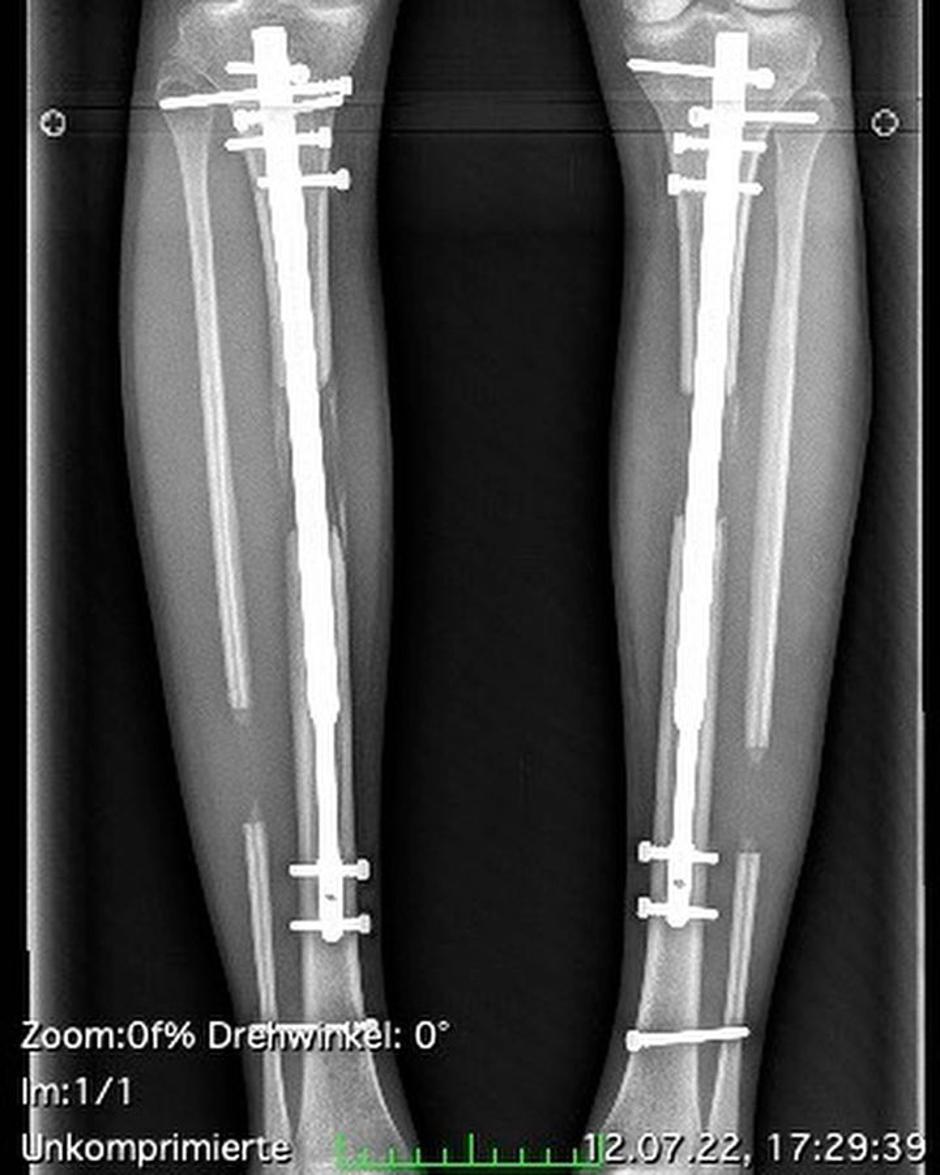

Med zapletenim posegom marca 2022 so 30-letnici prežagali kosti spodnjega dela noge in ji z obeh strani vstavili palice, s katerimi si je lahko nato samostojno z navijanjem podaljševala noge - centimeter za centimetrom. "Moje noge so sedaj dolge 116 centimetrov," je povedala lepotica in dodala, da bolečin ni več in da lahko spet počne vse, kar želi.